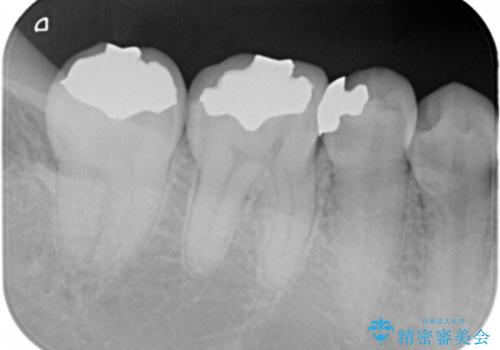

- 右下567 セラミックインレー 77,000円×3本費用は治療当時の料金となります

写真でもレントゲン画像でも確認できるように、段差がなく適合の良い詰め物を装着することができました。